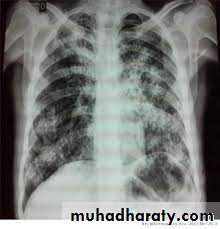

Histoplasmosis

It is a type of lung infection.It is caused by inhaling Histoplasma capsulatum fungal spores.

These spores are found in soil and in the droppings of bats and bird

It is disseminated form that occur in immunocompromised patient.